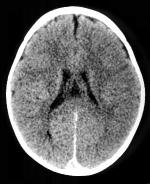

CT-scan van het hoofd

ct_schedel

Een CT-scan van de hersenen kan uitgevoerd worden met of zonder contrasttoediening. Welke methode gebruikt wordt is afhankelijk van de indicatie. In sommige gevallen kan het aangewezen zijn het onderzoek eerst zonder en daarna met contrast uit te voeren om een duidelijker beeld te verkrijgen in de pathologie van de patiënt.

Bij een trauma kan de radioloog de genomen beelden ook interpreteren in een venster waarin de beenderstructuren duidelijker zichtbaar zijn.

Indien er contrast toegediend zal worden, is het noodzakelijk om nuchter te zijn voor het onderzoek. Best is hiervoor om minstens vier uur voor het onderzoek niet te eten of te drinken.